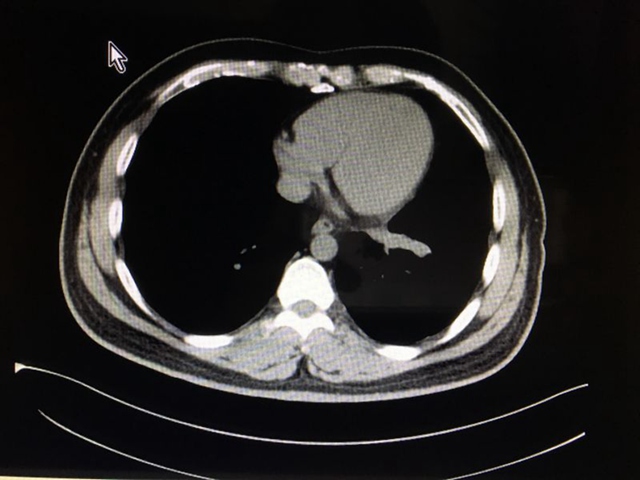

服用靶向药后(2016.2.6)CT影像: